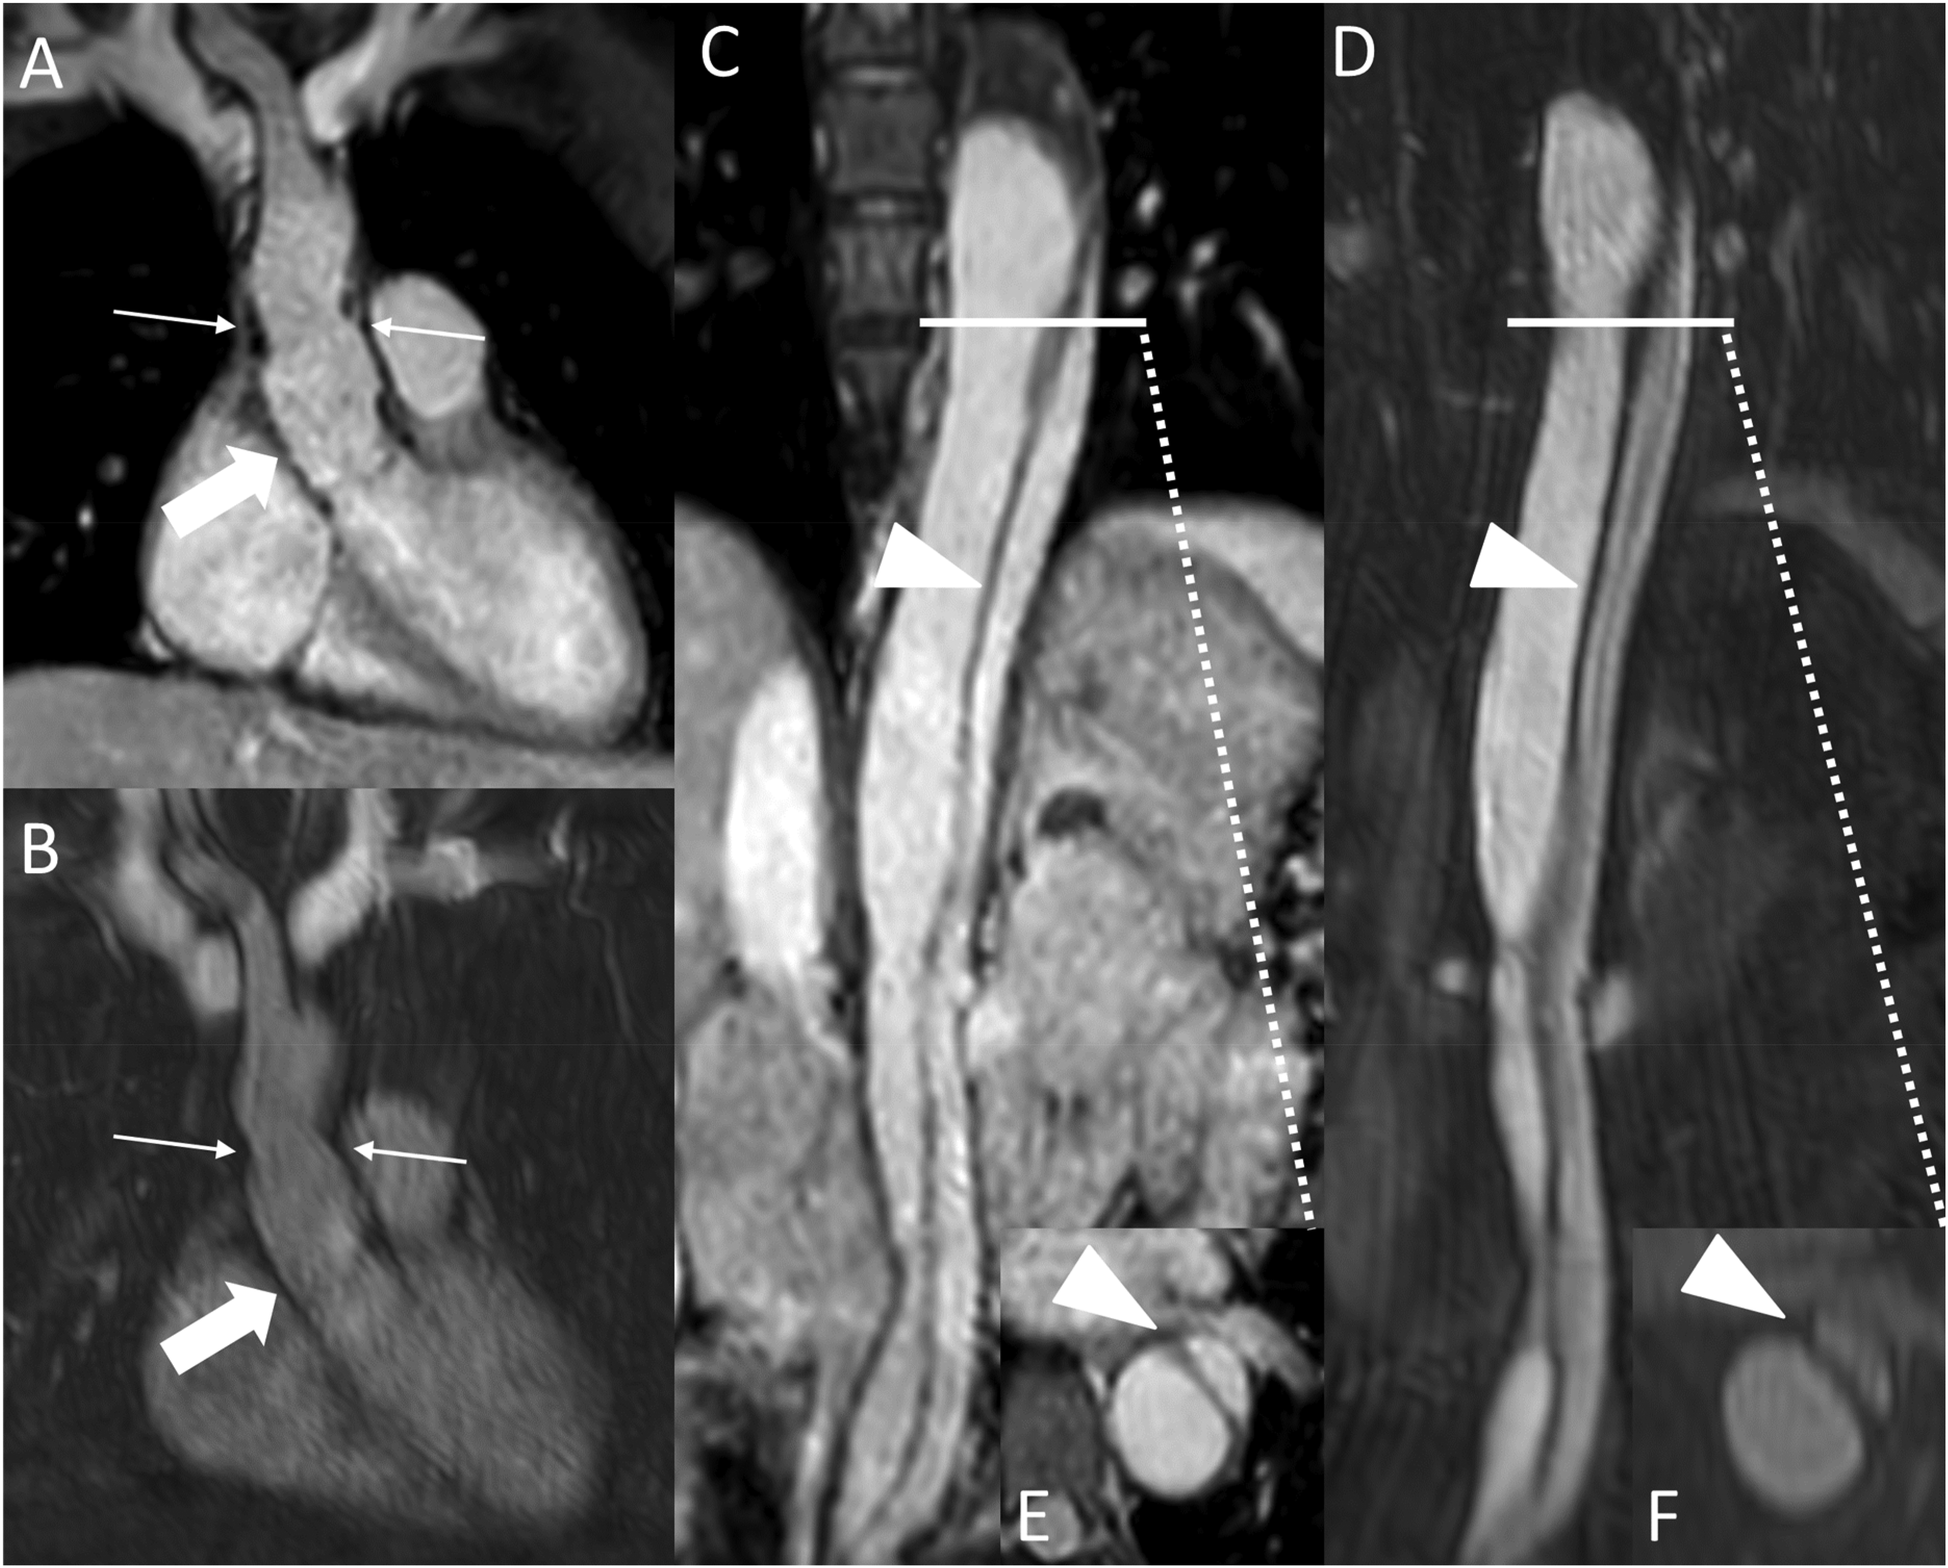

Figure 5

REACT [source images, water-only, coronal (A) and parasagittal planes (C)] and CE-MRA [source images, coronal (B) and parasagittal planes (D)] in a 27-year-old male after Bentall procedure due to Stanford type A aortic dissection. Note the superior delineation of the aortic graft (wide arrow: mid graft) and the left coronary artery (arrowhead) in REACT due to motion artifacts in CE-MRA. While the distal anastomosis and suture lines can be delineated in both sequences (thin arrows), REACT yields a superior delineation of these structures due to above mentioned artifacts in CE-MRA. CE-MRA, contrast-enhanced magnetic resonance angiography; REACT, relaxation-enhanced angiography without contrast and triggering.

Figure 6

REACT [(A), source image, water-only, coronal plane] and CE-MRA [(B), coronal plane] in a 44-year-old female after david-procedure due to Stanford type A aortic dissection. Note the higher vessel contrast at the level of the aortic graft (wide arrow: mid graft, thin arrow: distal anastomosis) in REACT due to mistiming in CE-MRA. The residual AD (arrowheads) affecting the descending and abdominal aorta can be equally delineated in both MRA sequences [REACT: (C) paracoronal reformation, (E) axial reformation; CE-MRA: (D) coronal reformation, (F) axial reformation]. CE-MRA, contrast-enhanced magnetic resonance angiography; REACT, relaxation-enhanced angiography without contrast and triggering.